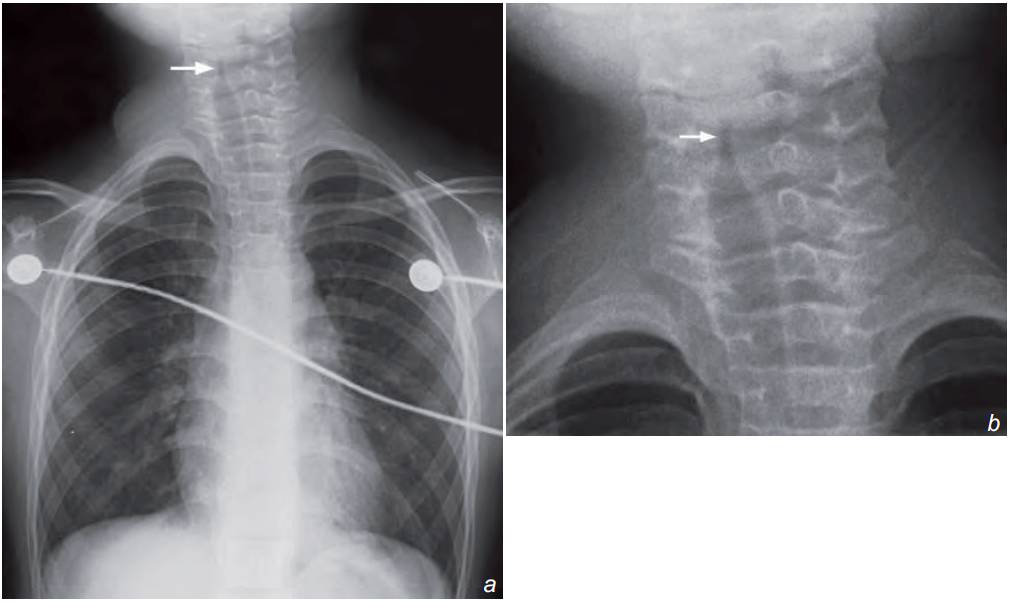

Chest x-ray shows characteristic subglottic inverted v ‘steeple sign’ with loss of the normal shoulders (arrow). CXR also helps to exclude foreign body inhalation as a cause of acute stridor.

The characteristic ‘steeple sign’ of the subglottic trachea with loss of the normal shoulders.